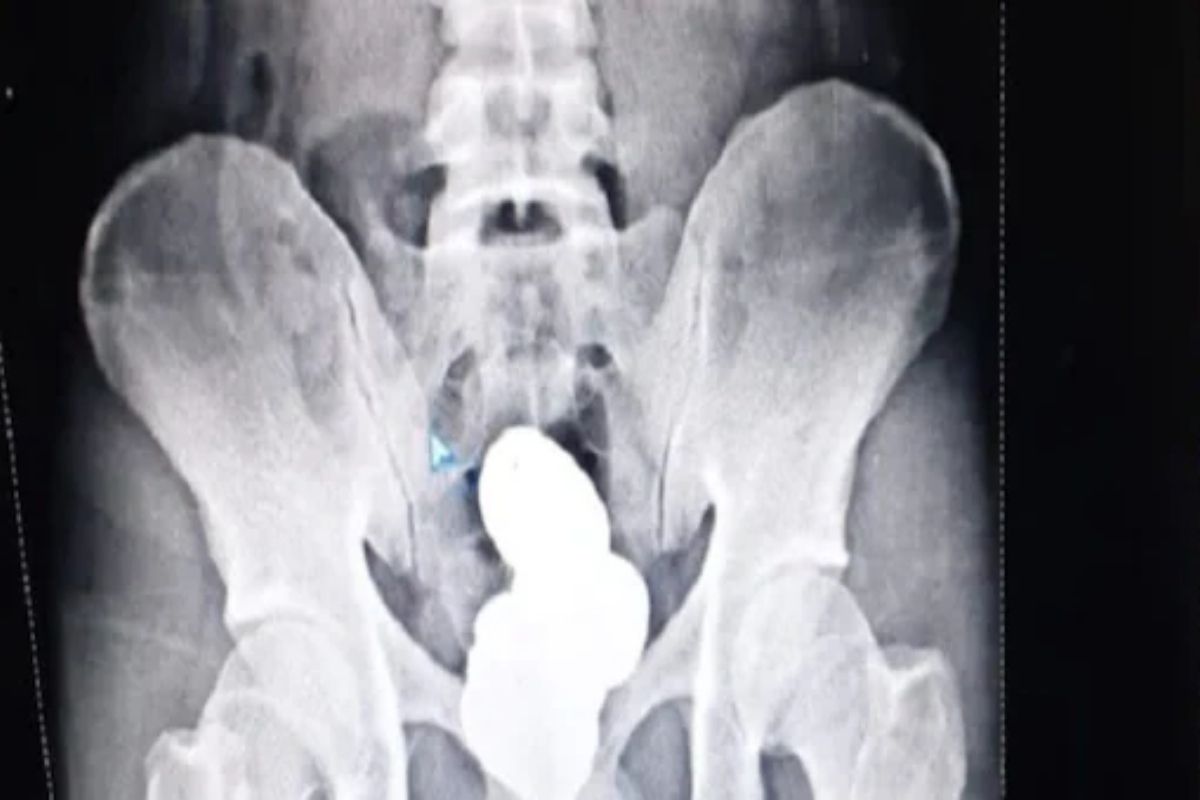

इम्फाळ, 6 ऑक्टोबर : तस्करी (smuggling) करण्याचं प्रमाण वाढत चाललं आहे. परदेशातून बेकायदेशीर वस्तू भारतात आणण्यासाठी तस्कर विविध मार्गांचा अवलंब करताना आपल्याला दिसून येतं. तसंच देशातही एका राज्यातून दुसऱ्या राज्यात तस्करी होते. ड्रग्ज (drugs), सोनं (gold), अफू, गांजा यांच्या तस्करीतून तस्करांना बक्कळ पैसा मिळतो. देशात सोन्याच्या तस्करीचं प्रमाण वाढलं आहे. पोलिसांना चकवा देण्यासाठी तस्कर (smugglers) नवनवीन क्लृप्त्या शोधत राहतात. सोन्याची तस्करी करण्यासाठी तस्कर विविध शक्कल लढवत असतात. तस्करांकडून सोन्याची तस्करी करण्याचा एक नवा प्रकार समोर आला आहे. सोन्याची तस्करी करण्यासाठी तस्करांनी लढवलेली भन्नाट शक्कल पाहून पोलिसांनाही आश्चर्य वाटलं. इम्फाळ विमानतळावर (Imphal airport) एका व्यक्तीला सोन्याची तस्करी करताना अलकीडेच अटक झाली. बेकायदेशीरपणे सोनं घेऊन जाताना या व्यक्तीने जी शक्कल लढवली त्याची बरीच चर्चा होत आहे. मोहम्मद शरीफ असं या तस्कराचं नाव आहे. तो इम्फाळहून दिल्लीला (Delhi) जात होता . विमानतळावरच्या सुरक्षा कर्मचाऱ्यांना त्याच्या हालचालींवर संशय आला. त्यांनी त्याला ताब्यात घेऊन तपासणीसाठी नेलं. त्या वेळी तो खूप घाबरलेला दिसला. सीआयएसएफ आणि कस्टम अधिकाऱ्यांनी त्याची कसून चौकशी केली. त्याच्या कपड्यांमधून आणि वस्तूंमधून त्यांना काहीही सापडलं नाही. यानंतर मोहम्मद शरीफ याचा एक्स-रे काढण्यात आला. एक्स-रेमध्ये जे दिसलं ते थक्क करणारं होतं. त्या व्यक्तीच्या गुदाशयात सुमारे 908 ग्रॅम सोनं होतं. हे सोनं त्याच्या पोटात पेस्टच्या स्वरूपात टाकण्यात आलं होतं. ही पेस्ट चार भागांमध्ये विभागली गेली आणि एक पॅकेट बनवून गुदाशयात लपवलं गेलं. हे ही वाचा- हायप्रोफाईल व्यापाऱ्याने केली आत्महत्या, पत्नीने कापून घेतला स्वतःचा गळा एक्स-रे पाहिल्यानंतर पोलिसांनी त्याची कसून चौकशी केली. त्यानंतर त्याने आपला गुन्हा कबूल केला. मोठ्या कष्टाने त्याने त्याच्या गुदाशयात खालून सोन्याची पेस्ट घातल्याचं त्याने सांगितलं. या सोन्याची किंमत 42 लाख रुपये आहे. कस्टम अधिकाऱ्यांनी त्याला अटक करून पुढील कारवाई सुरू केली. मोहम्मद शरीफ मूळचा केरळमधील कोळीकोडचा आहे. तो इम्फाळहून दिल्लीला सोनं बेकायदेशीरपणे घेऊन जात होता. इम्फाळमध्ये सोन्याची तस्करी मोठ्या प्रमाणावर केली जाते. काही दिवसांपूर्वी येथे अज्ञात वाहनातून तब्बल 43 किलो सोनं पकडलं होतं. येथून सोने घेऊन तस्कर ते इतर राज्यांमध्ये विकतात. मोहम्मद शरीफच्या माध्यमातून पोलीस त्यांच्या संपूर्ण टोळीचा छडा लावण्याचा प्रयत्न करत आहेत. मागच्या महिन्यात मुंबई विमानतळावर नार्कोटिक कंट्रोल ब्युरोने तीन महिलांना संशयावरून ताब्यात घेतलं. या महिलांनी त्यांच्या शरीरात ५ किलो सोन्याची बिस्किटं लपवली होती. महिलांनी त्यांच्या प्रायव्हेट पार्टमधून सोनं शरीरात टाकलं होतं.